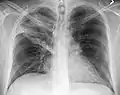

Normal AP CXR

AP CXR showing left lower lobe pneumonia associated with a small left sided pleural effusion

AP CXR showing right lower lobe pneumonia

AP CXR showing pneumonia of the lingula of the left lung

Right upper lobe pneumonia as marked by the circle.

Left upper lobe pneumonia with a small pleural effusion.

Right lower lobe pneumonia as seen on a lateral CXR